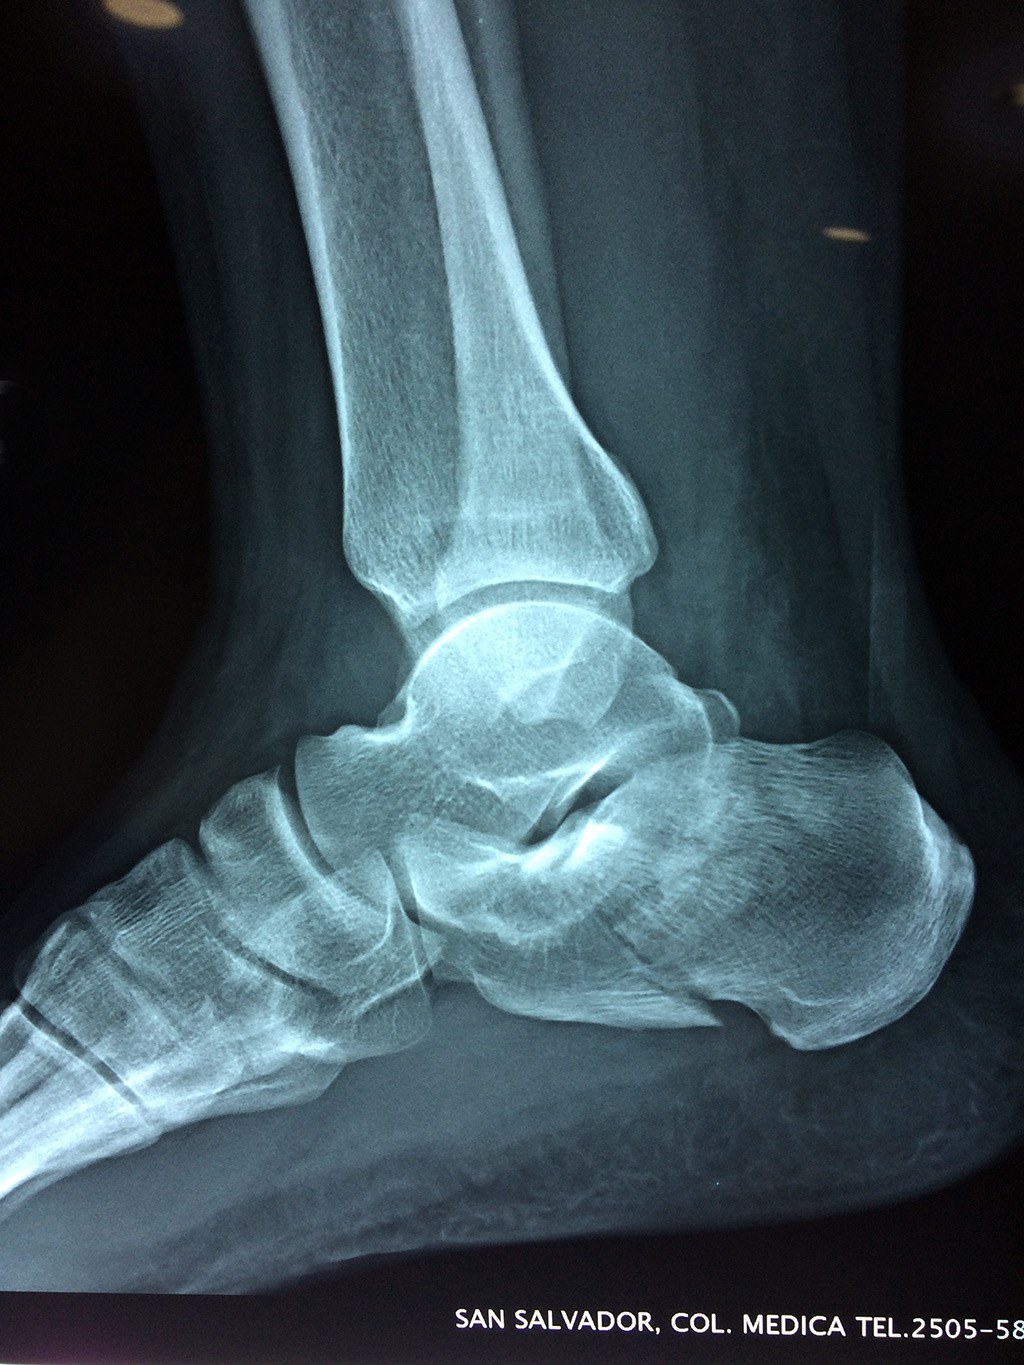

Este hueso constituye el talón del pie. Se encuentra en la parte inferior de la primera fila del tarso. Se articula con el astrágalo por arriba y con el cuboides por delante. Constituye el primer punto de apoyo del pie durante la marcha, situándose en una de las zonas peor irrigadas del cuerpo y protegido plantarmente por la almohadilla plantar de tejido adiposo, con función amortiguadora.

En su cara posterior recibe la inserción del tendón más plantar, implicada en diversas enfermedades como la fascitis o el espolón calcáneo. La posición del calcáneo en relación al astrágalo (articulación subastragalina) y al suelo determinan la posición de retropié en varo, en valgo o neutra.

Los retropiés varos y sobre todo, los retropiés valgos, son responsables de distintas enfermedades del aparato locomotor y contribuyen a que aparezcan alteraciones de la marcha normal fisiológica, con consecuencias clínicas importantes (dolor, sobrecargas, aplanamiento, fatiga muscular, juanetes, etc.) tanto a nivel de pie como a nivel del miembro inferior.